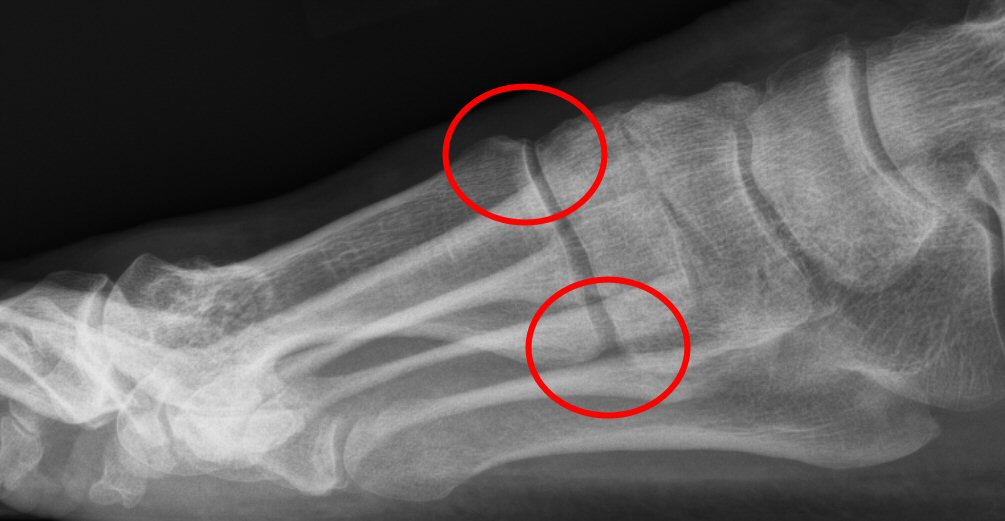

Tecken till instabilitet i TMT1: minskad ledspringa dorsalt